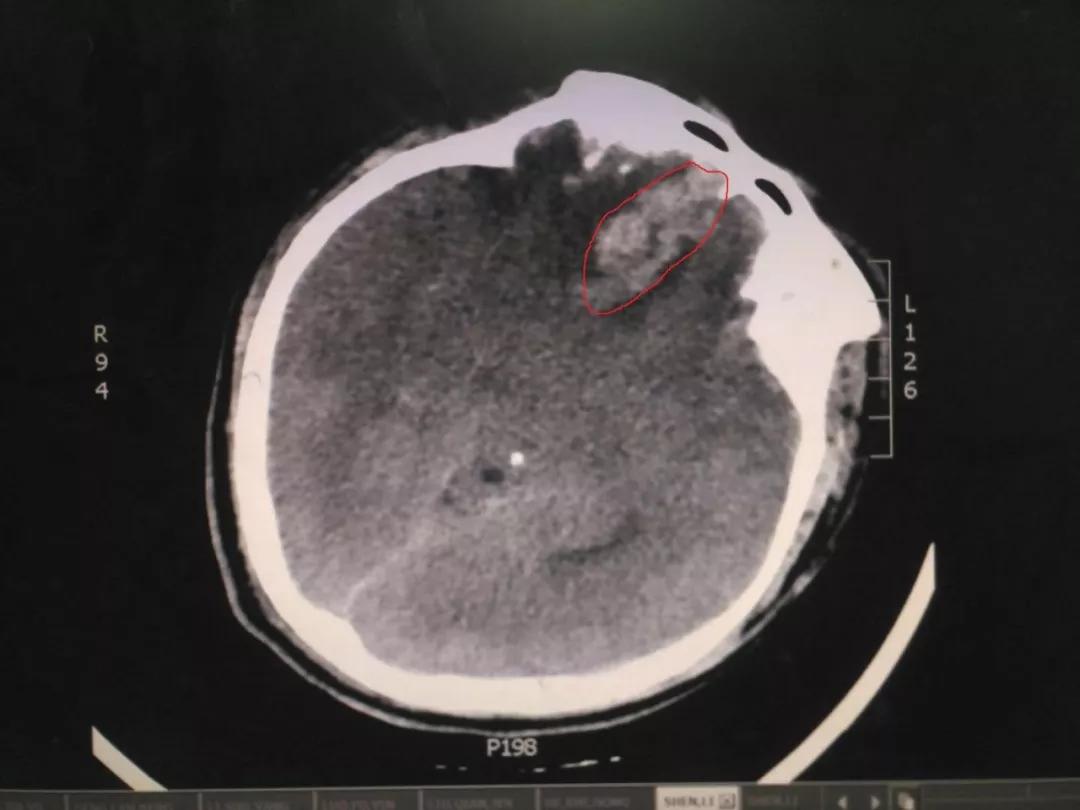

初步诊察发现患者右侧瞳孔散大,CT结果显示右侧额叶脑挫裂伤,部分血肿位于前颅凹底,位置深,清除困难,这给治疗带来了一定的难度。王占尧主任医师随即决定应用神经内镜辅助清除血肿,并采用右侧额颞弧形切口,避免采取传统的双额冠状切口,骨窗大小仅有4cmX4cm,大大减少了手术创伤,也相应减少了住院手术的费用,减轻了患者负担。术后第二天,患者意识恢复,复查CT显示血肿清除效果满意。